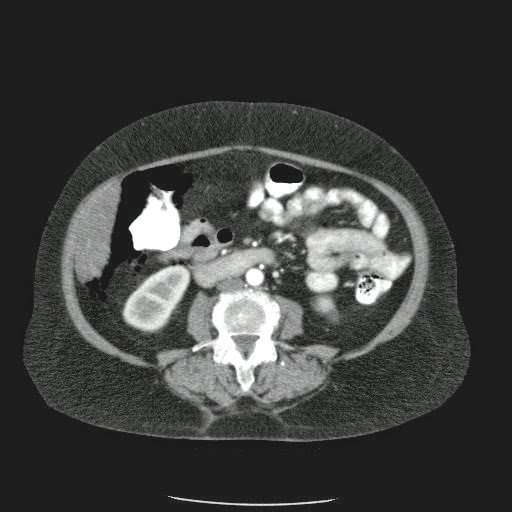

- ¿Hallazgos Escanografia?

2. Hay una colección de la pared abdominal en el flanco derecho, que realza en la periferia con el contraste, e intraabdominal tiene aire pero no me parece colección intraabdominal porque la grasa no está alterada.